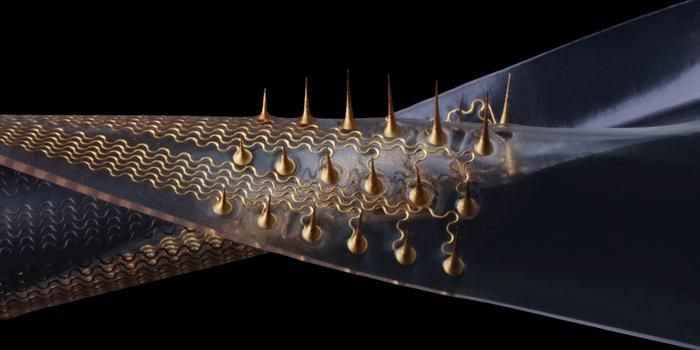

FEB 05, 2025TechnologyHow can the field of synthetic biology help improve engineered living materials (ELMs)? This is what a recent study publ ...

JAN 30, 2025TechnologyCan organic electronics be used to mimic biological processes like sensory systems? This is what a recent study publishe ...

DEC 12, 2024TechnologyHow can implantable sensors help patients during their recovery? This is what a recent study published in npj Regenerati ...